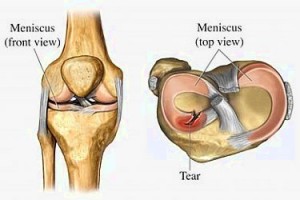

Meniscal tear is an injury or a tear in the meniscus which act as lubricators, shock absorbers, stabilizers, and load distributors between knee joints. It is made up of cartilages which consist of two disks- the medial (inside) and lateral (outside) meniscus.

• Medial Meniscus is generally more prone to injuries. It is a structure that separates the tibia (shinbone) from the femur (thighbone). It serves as a shock absorber to help reduce friction between the bones for smoother and more balanced movements.

• Lateral Meniscus is a thick pad crescent shaped form that covers most parts of the articular surface. It acts as surface smoother for joints to move freely.